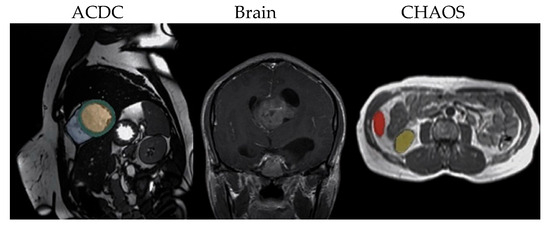

The rapid development of Generative Adversarial Networks (GANs) has transformed medical image processing, enabling realistic image synthesis, augmentation, and restoration. This study presents a comparative evaluation of three representative GAN architectures, Pix2Pix, SPADE GAN, and Wasserstein GAN (WGAN), across multiple medical imaging tasks,

The rapid development of Generative Adversarial Networks (GANs) has transformed medical image processing, enabling realistic image synthesis, augmentation, and restoration. This study presents a comparative evaluation of three representative GAN architectures, Pix2Pix, SPADE GAN, and Wasserstein GAN (WGAN), across multiple medical imaging tasks, including segmentation, image synthesis, and enhancement. Experiments were conducted on three benchmark datasets: ACDC (cardiac MRI), Brain Tumor MRI, and CHAOS (abdominal MRI). Model performance was assessed using Fréchet Inception Distance (FID), Peak Signal-to-Noise Ratio (PSNR), Structural Similarity Index (SSIM), Dice coefficient, and segmentation accuracy. Results show that SPADE-inpainting achieved the best image fidelity (PSNR ≈ 36 dB, SSIM > 0.97, Dice ≈ 0.94, FID < 0.01), while Pix2Pix delivered the highest segmentation accuracy (Dice ≈ 0.90 on ACDC). WGAN provided stable enhancement and strong visual sharpness on smaller datasets such as Brain Tumor MRI. The findings confirm that no single GAN architecture universally excels across all tasks; performance depends on data complexity and task objectives. Overall, GANs demonstrate strong potential for medical image augmentation and synthesis, though their clinical utility remains dependent on anatomical fidelity and dataset diversity.